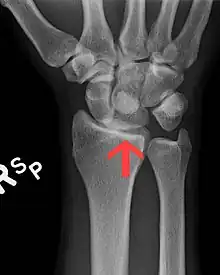

| A lateral X-ray of the wrist showing a lunate dislocation | |